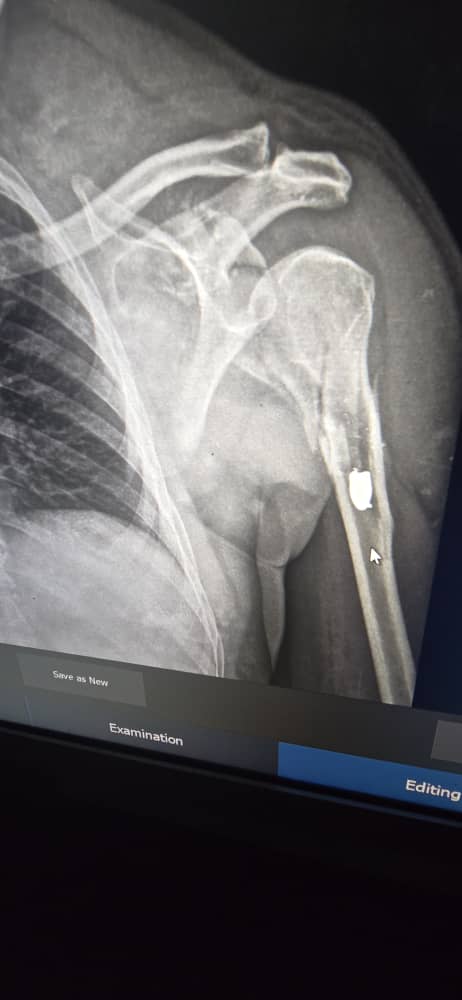

وأوضح المصدر أن الطلقة ما تزال مستقرة في جسد القب، مرجحًا أنها أطلقت من مسدس، مشيرًا إلى أنها تسببت في كسر عظم الكتف باليد اليمنى.

ولفت إلى أن حالة القب مستقرة، ويحتاج إلى فترة راحة قبل إجراء تدخل جراحي لنزع الطلقة المستقرة في جسده.